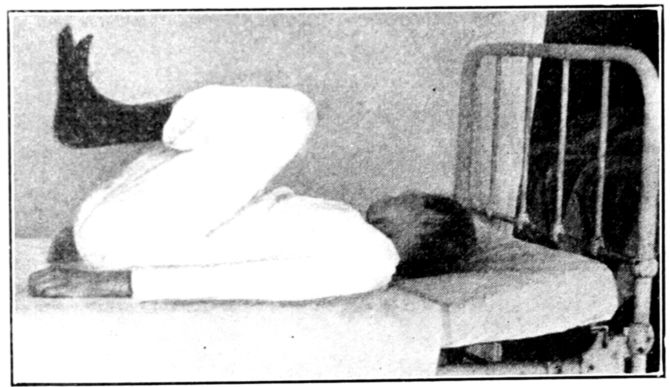

| 40. | Patient in right-angled position to relieve varicose veins | 138 |

| 41. | Elevated Sims position | 139 |